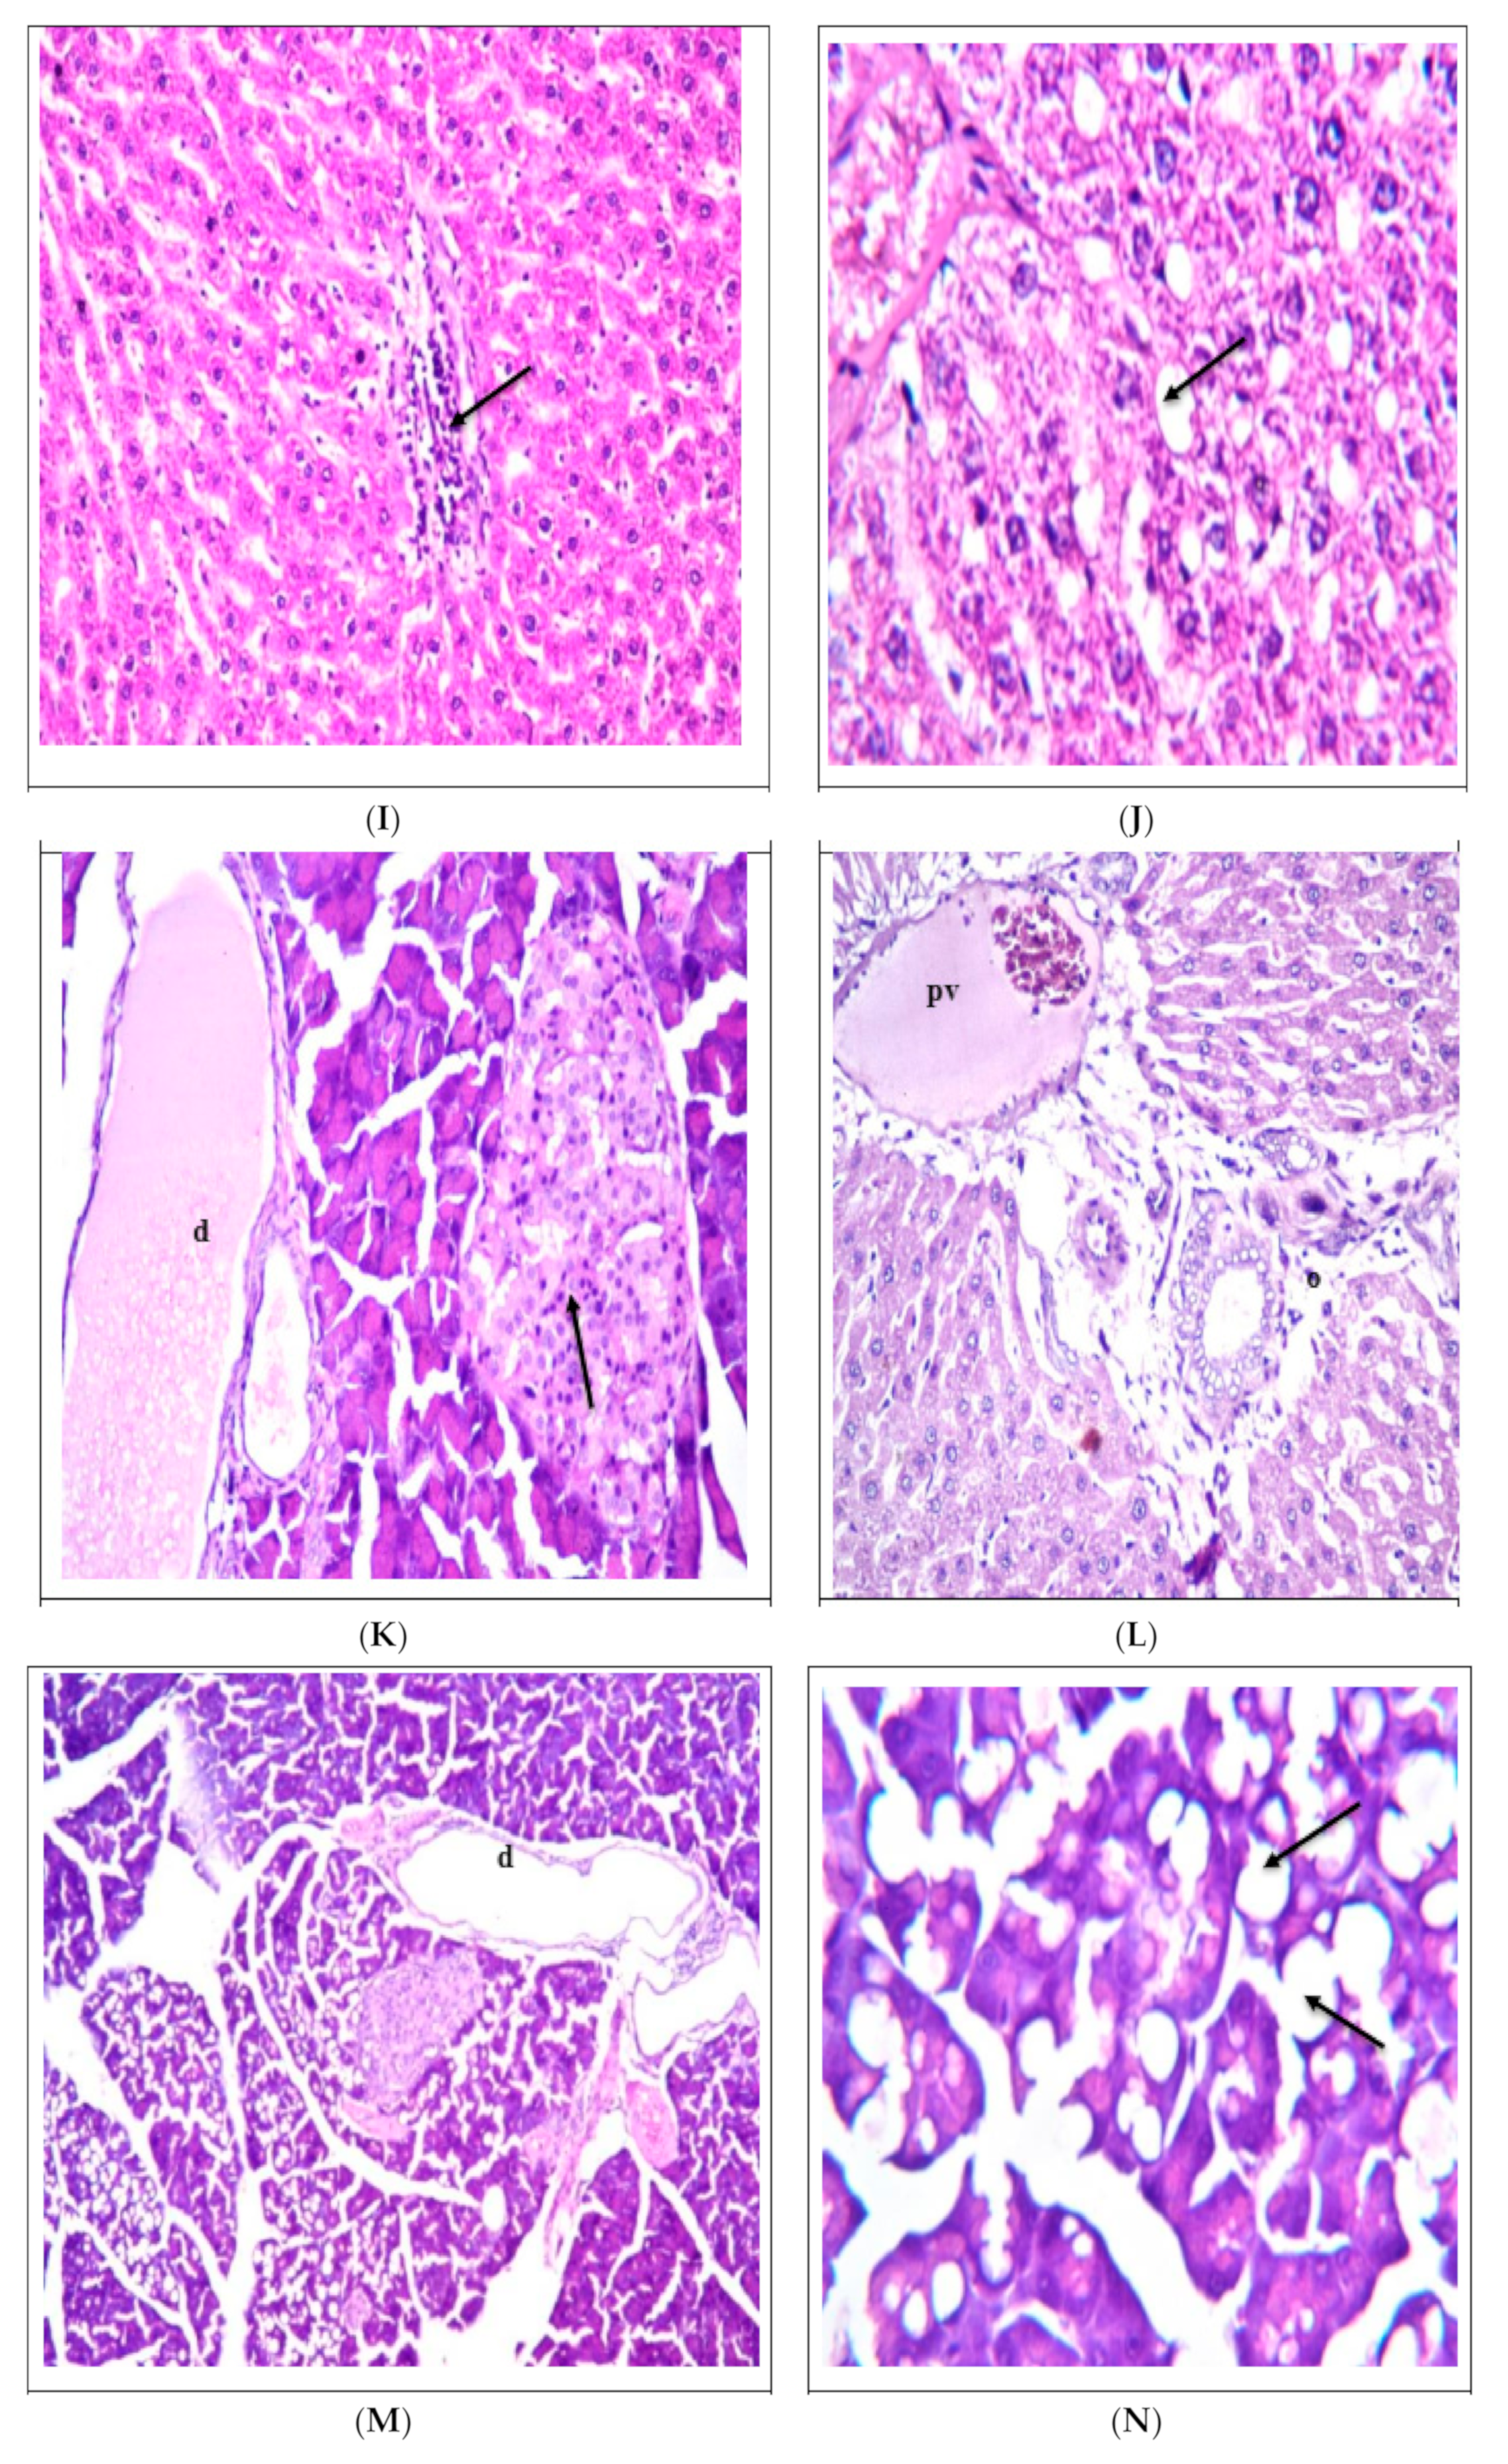

3.4. Effect of Cupcakes Supplementation on the Liver and Pancreas Histopathology

The negative control group displayed normal pancreas and liver structures, with no histological alterations, as indicated by Figure 1A,B and Table 10. On the other hand, severe alterations were observed in the positive control group, with degenerations in both pancreas and liver structures, as shown in Figure 1C–E and Table 10. When diabetic rats were fed on the cupcake control sample, moderate alterations were found in pancreas structures due to degenerations. However, normal hepatic structures were observed, as displayed in Figure 1F–J and Table 10. In the case of cupcakes supplemented with BPP, moderate changes were detected in the structure of the pancreas islet of Langerhans, but no degenerations were noted in hepatocytes (Figure 1K,L and Table 10). Likewise, feeding diabetic rats with cupcakes containing CLP revealed mild to moderate changes in the liver, but no effects were observed in the pancreas islet of Langerhans, as detected in Figure 1M–P and Table 10. Additionally, no significant histopathological changes were detected in the pancreas, and only moderate changes were observed in the liver in diabetic rats fed on cupcakes containing SLP (Figure 1Q–S and Table 10). Interestingly, a mixture of SLP and BPP in cupcakes caused no histopathological alteration in the pancreas, while moderate degenerations were detected in the hepatocytes (Figure 1T,U and Table 10). The most exciting finding was that diabetic rats fed on cupcakes supplemented with a mixture of SLP and CLP showed no histopathological alterations in the pancreas and liver, as shown in Figure 1V–X and Table 10. These results suggest that the additive effect of the supplements reduces T2DM complications.

The above findings agreed with Wang et al. [52], where feeding diabetic rats with banana fibers noticeably reduced hepatocellular steatosis, fewer lipid droplets, relatively less inflammatory cell infiltration, and ameliorative effects on liver histopathology in diabetic mice. On the other hand, the number and volume of pancreatic islets in groups fed on banana fibers increased, and the pancreatic tissue lesions were improved. Along the same line, the histologic evaluation of the hepatic tissues performed by Assi et al. [61] showed a significant decrease (p < 0.05) in liver injuries in the diabetic group treated with Stevia compared to the diabetic control rats.

Figure 1. Effect of replacement sugar in cupcake formula with stevia leaves and agro-wastes (banana peels and carrot leaves) on the liver and pancreas histopathology in T2DM mice. (A) The pancreas of the rats in group 1 displayed a typical histological structure, with the islet of Langerhans cells (L) functioning as the endocrine portion and the surrounding akin (a) serving as the exocrine. (B) In group 1, the rat liver exhibits a normal histological structure with the central vein (cv) and surrounding hepatocytes (H) in the parenchyma. (C) In group 2, there were areas of rat tissue that displayed atrophy and a decrease in the size of Langerhans cells in the islets. (D) In group 2, the rat’s liver displays hepatocyte degeneration (d) throughout the parenchyma. (E) In group 2, the rat liver displays severe dilatation of the portal vein (pv) accompanied by edema (o) in the portal area. (F) In group 3, the rat’s pancreas exhibits atrophy and necrobiotic changes in the islet of Langerhans cells (nL), along with the dilation of the pancreatic duct (d). (G) In group 3, the rat’s pancreas exhibited atrophy of the islet of Langerhans (aL), which can be identified through magnification. (H) In group 3, the rat’s liver displays portal vein dilatation alongside bile duct dilatation and hyperplasia (hbd), edema (o), and a small number of inflammatory cells (arrow) infiltrating the portal area. (I) In group 3, the rat liver exhibits a concentration of inflammatory cells in the parenchyma, as indicated by an arrow. (J) In group 3, there are some individual hepatocytes showing fatty change, as indicated by an arrow. (K) In group 4, the rat’s pancreas indicates necrobiotic changes (pointed by an arrow) in a few islets of Langerhans cells, along with the expansion of pancreatic (d) ducts. (L) In group 4, there is evidence of liver damage with a dilated portal vein (PV) and edema (O) in the portal area. (M) In group 5, the rat’s pancreas displays duct dilation (d). (N) In group 5, the rat’s pancreas is magnified to identify the fatty change in the acinar lining epithelium, as indicated by the arrow. (O) The rat’s pancreas from group 5 exhibits congestion in its stromal blood vessels. (P) In group 5, the rat’s liver exhibits dilatation of both the central vein (cv) and portal vein (pv). (Q) In group 6, the rat’s pancreas displays intact islets of Langerhans cells, as indicated by the arrow. (R) In group 6, the rat’s liver exhibits hepatocyte degeneration, as the arrow indicates. (S) In the sixth group, the rat’s liver displays portal vein (pv) congestion and edema, along with a small number of inflammatory cells in the portal area. (T) In group 7, the rat’s pancreas exhibits a histological structure that appears normal and intact, as indicated by the arrow. (U) In group 7, the rat’s liver displays hepatocyte degeneration around the central vein, as indicated by the arrow. (V) The pancreas from group 8 rats displays a typical histological structure of Langerhans cells (L) in the islets. (W) The liver sample from group 8 exhibits a normal histological structure. (X) In group 8, the rat’s liver exhibits dilatation and congestion in both the central vein (cv) and portal vein (pv).